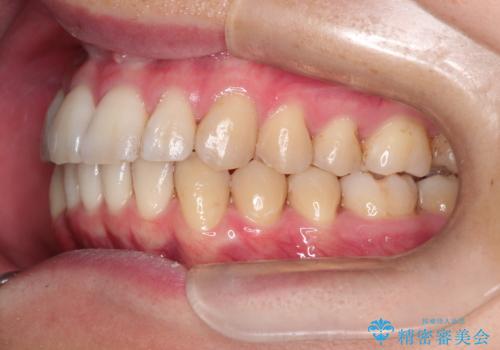

前歯の凸凹をきれいにしたい。インビザラインによる治療

- 前歯の凸凹を主訴に来院された患者様です。

インビザラインにて治療を行いました。